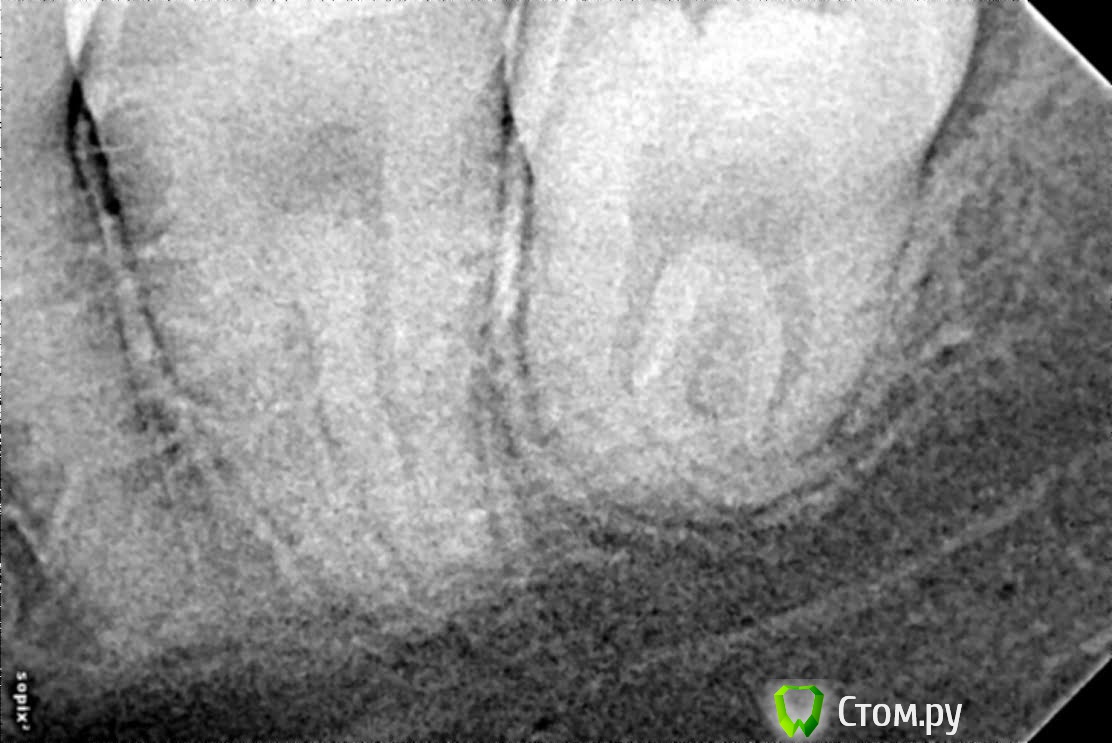

jackos Опубликовано 3 августа, 2014 Поделиться Опубликовано 3 августа, 2014 (изменено) Здравствуйте. Во время прорезывания 8 зуба распухла десна, затем воспаление перешло на десны 6-7 зуба.После посещения стоматолога сказали, что это выходит гной из 6 зуба и только удалять. Так ли это, обычным лечением уже ничего не сделать? До роста зуба мудрости зуб никак не беспокоил,лечил только от кариеса. Спасибо. Изменено 3 августа, 2014 пользователем jackos Ссылка на комментарий

red_butler Опубликовано 3 августа, 2014 Поделиться Опубликовано 3 августа, 2014 На снимке, проблем с 6 зубом не вижу, мудрый удаляйте 1 Ссылка на комментарий

Гарриевич Опубликовано 3 августа, 2014 Поделиться Опубликовано 3 августа, 2014 по снимку проблем с 6кой нет Ссылка на комментарий